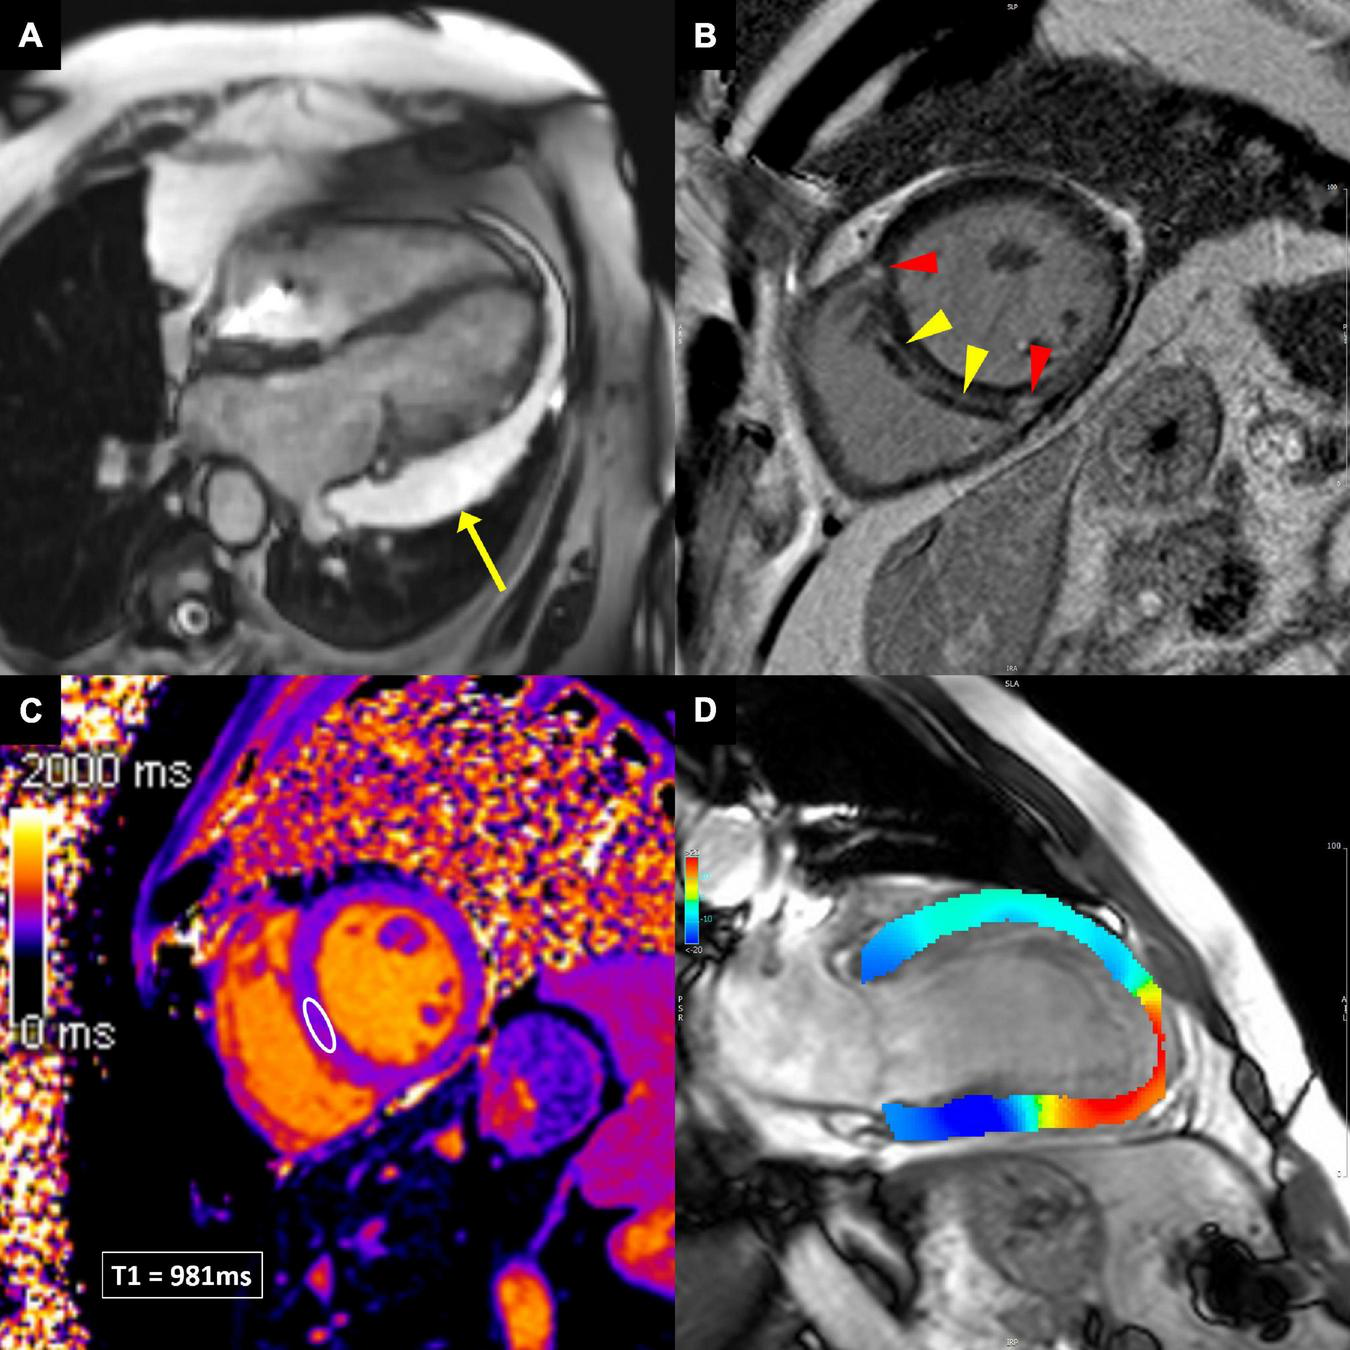

FIGURE 5

Cardiovascular magnetic resonance techniques to evaluate cardiotoxicity. (A) Balanced steady-state free precession cine image in breast cancer patient demonstrating large pericardial effusion next to the lateral wall of the left ventricle (yellow arrow). (B) Late gadolinium enhancement image, showing linear midwall myocardial fibrosis (yellow arrowheads), indicating non-ischemic dilated cardiomyopathy. In addition, the anterior and inferior right ventricular insertion point fibrosis is present (red arrowheads), which is a non-specific finding. (C) Native T1 image, allowing T1 measurements in any desired myocardial area of interest (white ellipse in the ventricular septum). (D) Feature-tracking strain image, showing impaired longitudinal strain in the apex and apical inferior wall (red color), consistent with apical myocardial infarction.

T2-weighted short tau inversion recovery and bright blood T2-weighted sequences are most commonly used to evaluate myocardial edema (58).

Late gadolinium enhancement (LGE) is considered the gold standard for non-invasive evaluation of myocardial fibrosis (58). About 10–20 min after gadolinium-based contrast agent injection, the difference in contrast washout between the normal and abnormal myocardium can be visualized so that the normal myocardial appears black and areas of fibrosis appear white (58). However, LGE is sensitive to any kind of extracellular volume expansion and delayed contrast washout might as well be present in myocardial edema or other extracellular deposits (e.g., amyloidosis). The pattern and distribution of LGE can imply ischemic or non-ischemic etiology of myocardial disease (Figure 5B) (59, 60).

Novel CMR sequences for detection of myocardial inflammation, edema and fibrosis allow quantification of changes in T1 and T2 relaxation times and computation of extracellular volume (ECV) (Figure 5C) (60, 61). These techniques can detect diffuse processes involving the entire myocardium, unlike the standard edema and LGE techniques, which rely on signal intensity differences between normal and diseased myocardium. Furthermore, direct quantification improves diagnostic confidence and intra- and inter-observer variability (62). In the setting of myocardial inflammation/edema, T2 mapping is the most sensitive parameter (62). Increased native T1 values can reflect both edema and fibrosis, while ECV is the most sensitive parameter to detect myocardial fibrosis.

Several CMR techniques have been developed in the past to analyze myocardial deformation, e.g., myocardial tagging, displacement encoding with stimulated echoes, strain-encoded imaging. Their main shortcoming was the need for special scan sequences. Recently, feature-tracking CMR has been developed, which is based on tissue tracking algorithm applied to standard cine images during postprocessing, similar to speckle-tracking echocardiography (Figure 5D) (63). LV strain (and strain rate) can be measured in all three directions of cardiac motion—longitudinal, circumferential, and radial. Feature-tracking CMR has been increasingly utilized in various cardiac diseases and has shown incremental prognostic value to common clinical and CMR imaging risk factors, including LVEF and LGE (64–67).